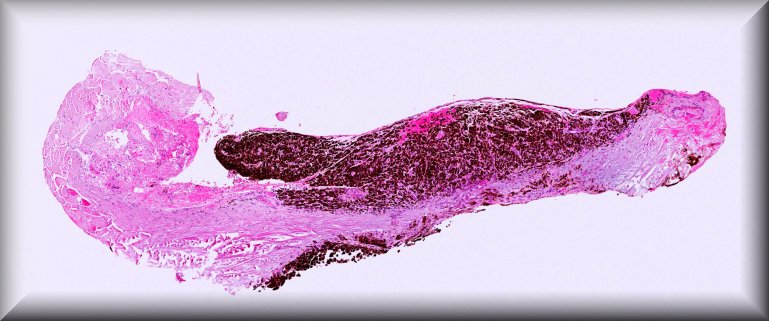

Daniela Süsskind (Tuebingen): Rapidly growing tumor of the conjunctiva in an 86 years old woman presenting as a masquerade syndrome with signs of intraocular inflammation. |